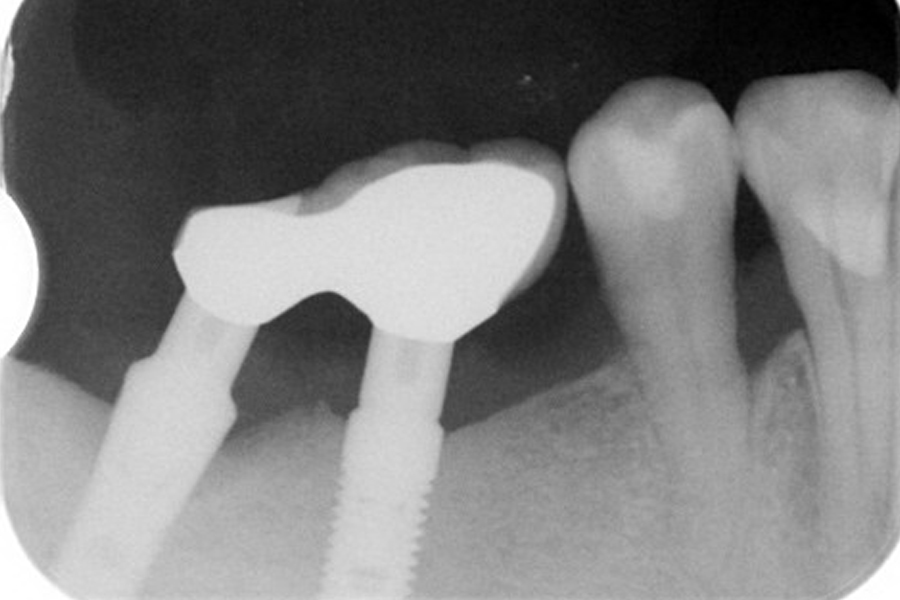

こちらの患者様は2002/02/21、16年前に当医院で私がインプラント手術致しました。

16年後の定期健診でインプラント周囲炎を起こしていることを発見致しました。

レントゲン上で左のインプラント周囲の骨が吸収しているのが観察されます。(2018年2月撮影)

インプラントは骨と結合(oseoinyerration)しやすいように表面の構造が塑像になっていてそのことが一旦、プラークで汚染されるとインプラント体を清掃して無菌的にしてインプラント周囲炎を治癒させる方法がありませんでした。

Er:Yagレーザーによりこの塑像な構造を洗浄して歯石・細菌性プラークを綺麗に除去することが出来るようになりました。

手術時と術後4ヶ月の写真です。

4ヶ月前のオペ時のビデオです。